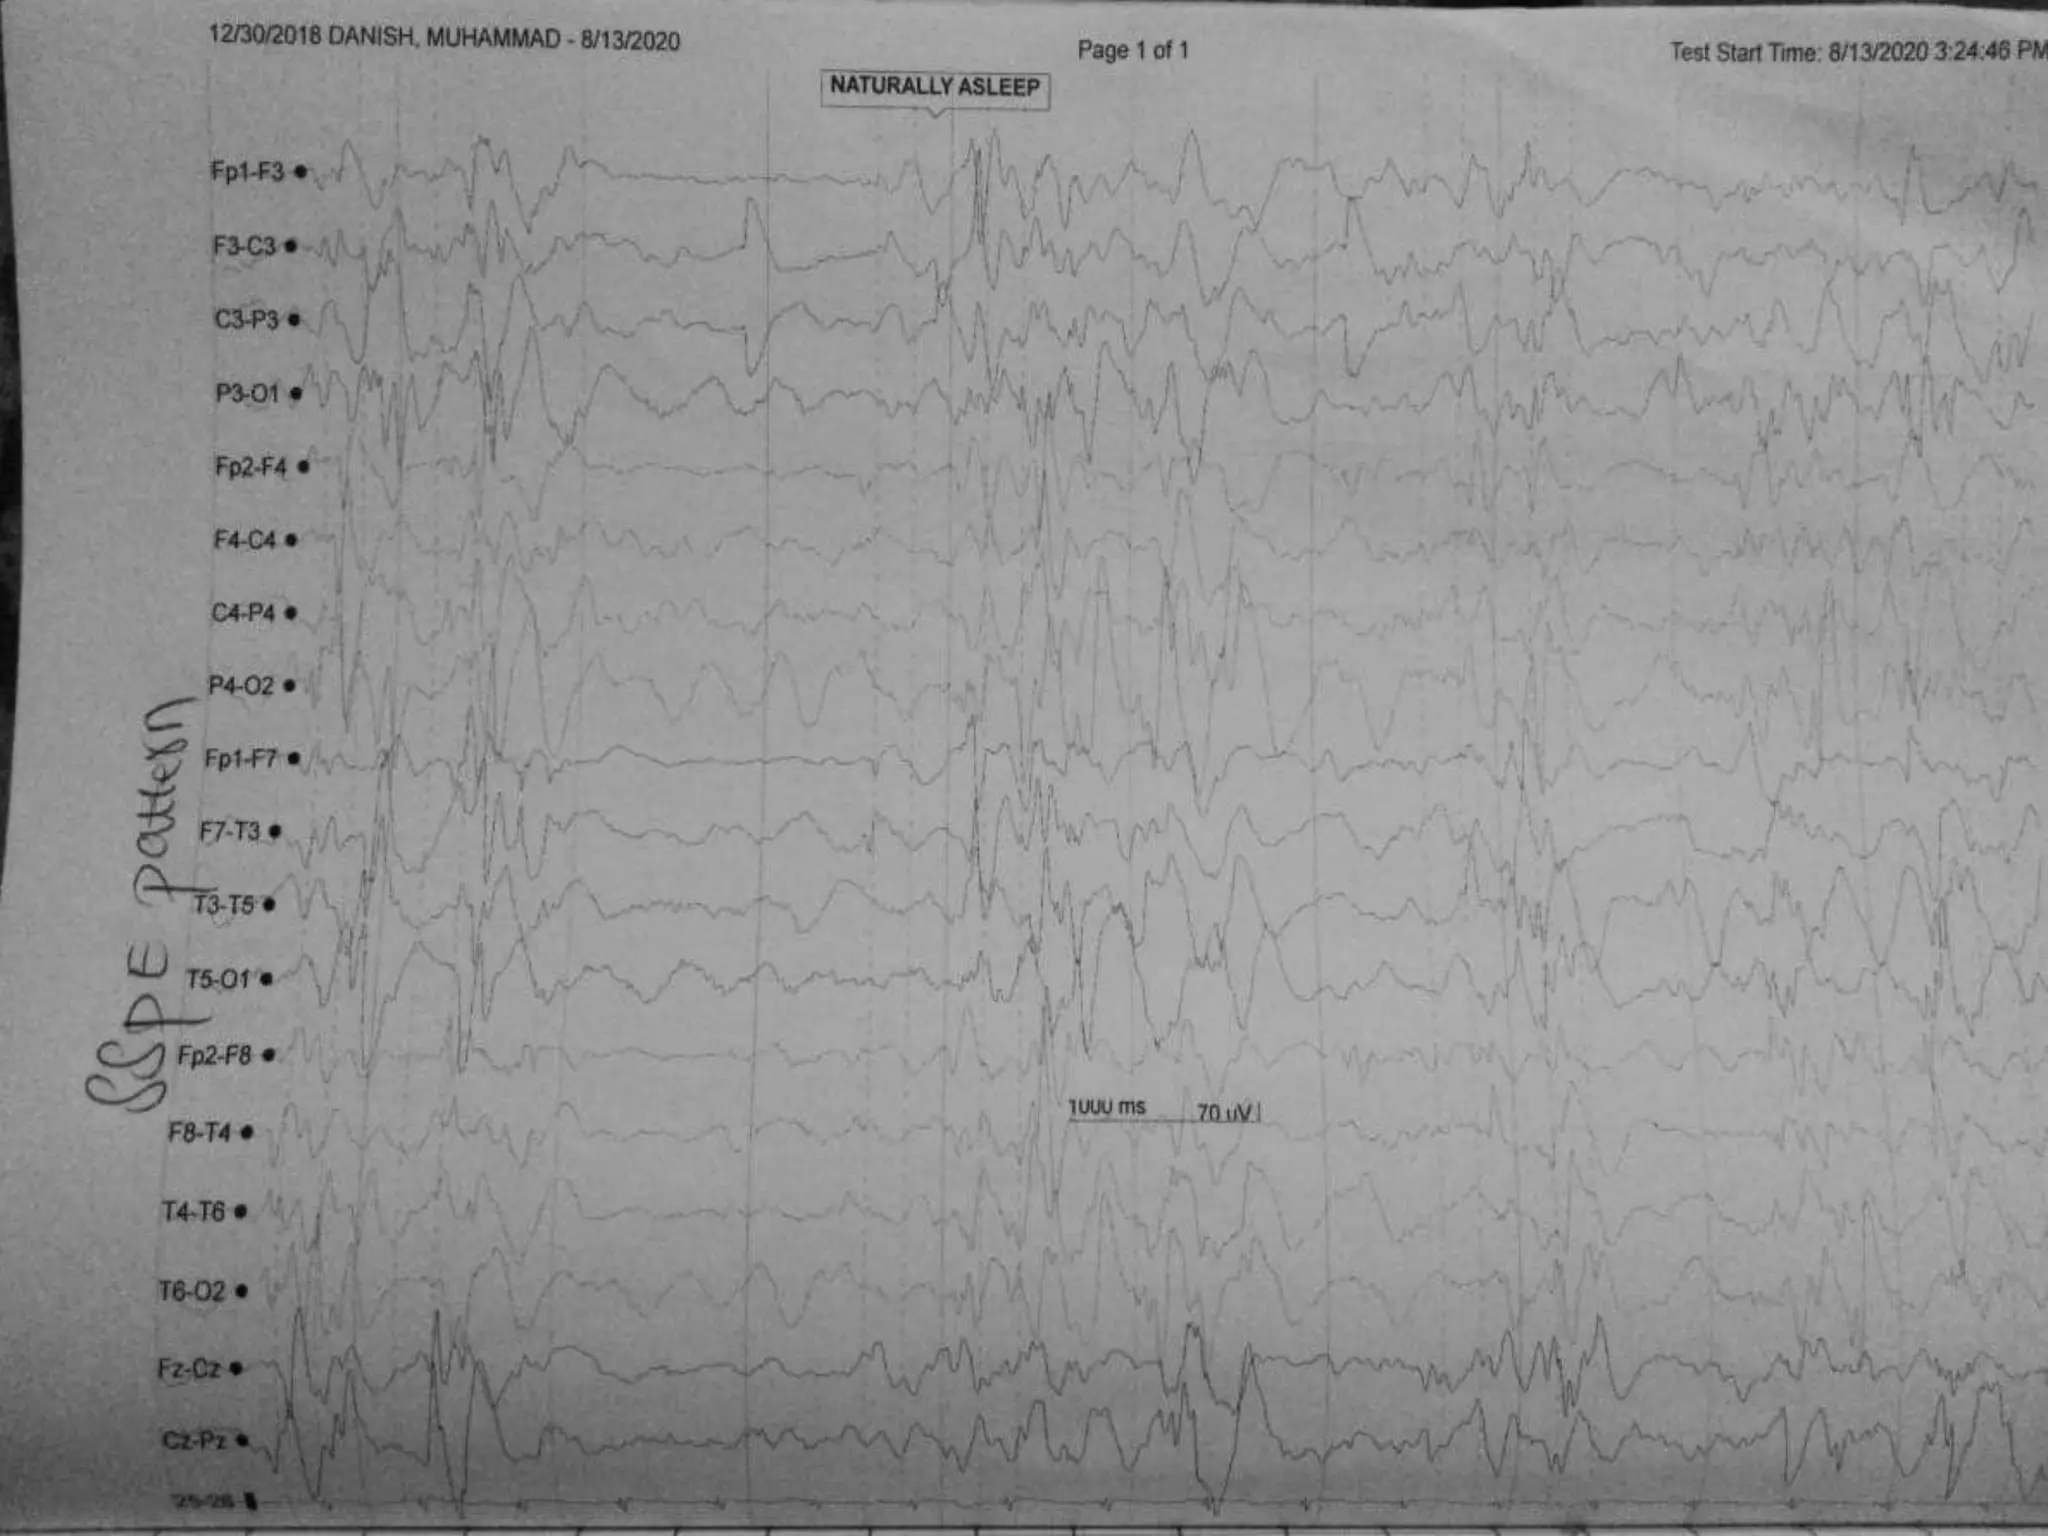

SUBACUTE SCLEROSING

PANENCEPHALITIS

• Repetitive bursts of high voltage spike, sharp and slow wave complexes,

recurring after every 4-15 seconds.

• More prominent in awaking state.

• Gen. but maximum over fronto-central areas.

• Frequency ranges 4-15/sec

• All the waves are Stereotyped (morphologically similar)

• Bilaterally synchronous

• Periodic high voltage 300-1500uv of sharp and slow waves complex with an

irregular delta wave superimposed.

• CLINICALLY:

• PATIENT WILL BE MENTIALLY RETARDED .

• It relates with measles and myoclonic jerks

• JERKS WILL BE TIME LOCKED

• It is an inflammatory disease that occurs in children and adolescents and is

believed to be caused by measles virus